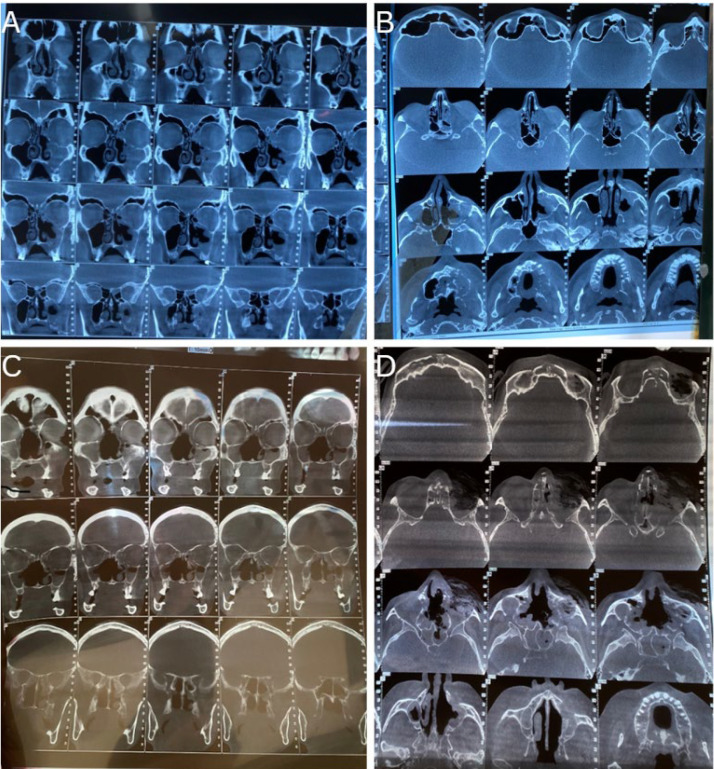

Abstract Image